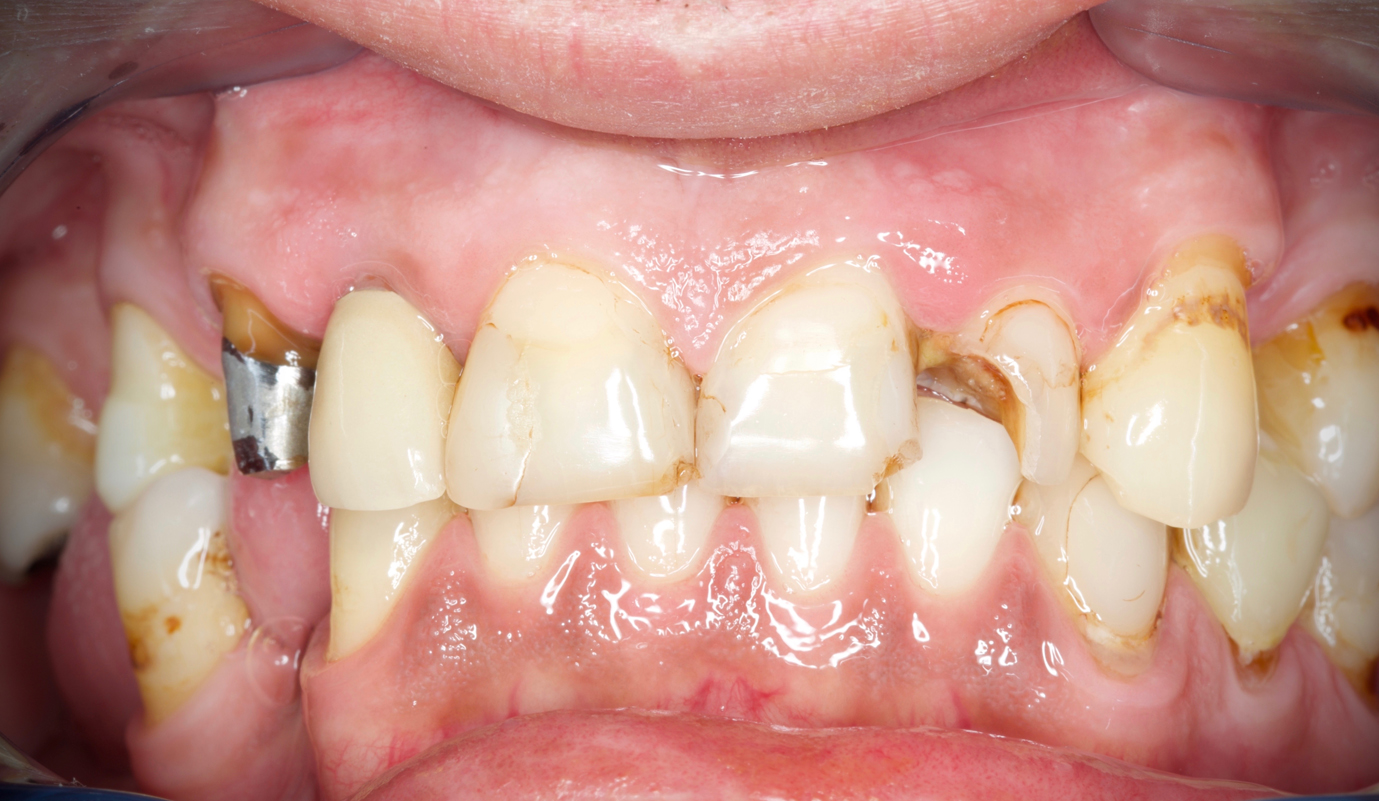

- Melhorar a aparência dos dentes quebrados ou danificados por cáries;

Casos de prótese fixa sobre dentes